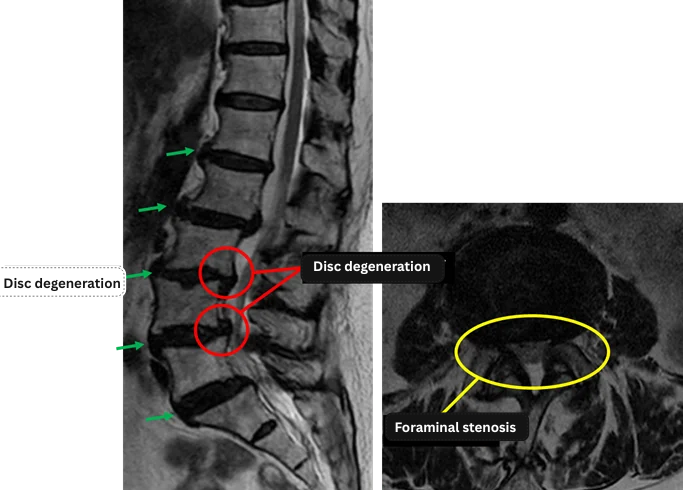

L1/2: Disc degeneration, disc bulging

L2/3: Disc degeneration, disc bulging, bilateral foraminal stenosis

L3/4: Disc degeneration, disc herniation, bilateral foraminal stenosis

L4/5: Disc degeneration, disc herniation

L5/S1: Disc degeneration, disc bulging, bilateral foraminal stenosis

The above findings were also observed on the imaging.

Disc degeneration, disc herniation, and bilateral foraminal stenosis were identified at L2/3, L3/4, L4/5, and L5/S1, and these findings were considered highly likely to be the cause of the patient’s primary symptoms.